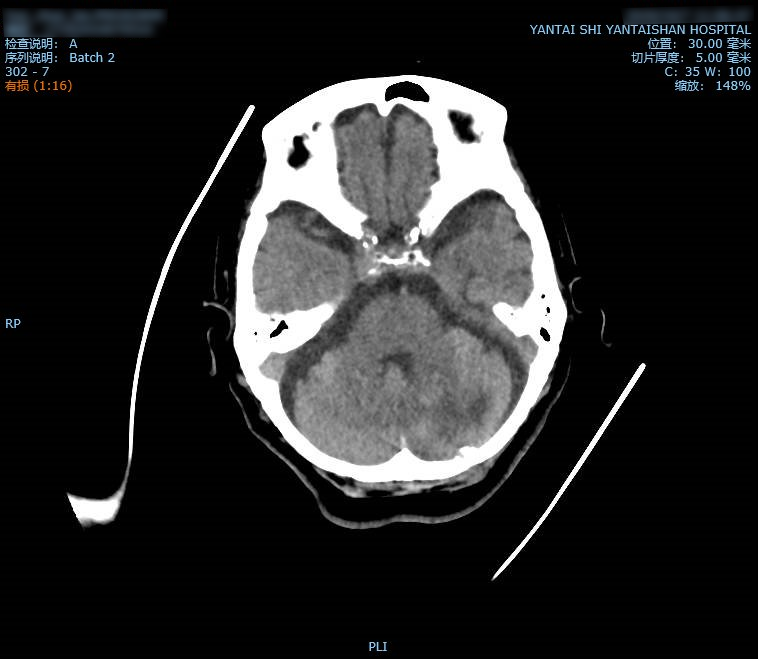

图中所示为患者入院时左侧小脑出血

前段时间,这位患者突然出现神志恍惚,并伴有呕吐,她被紧急送往烟台山医院东院区,当时她的血压高达230/120mmHg,颅脑CT提示左侧小脑出血,出血量约20ml。患者病情危重,随时都有呼吸心跳停止的可能。